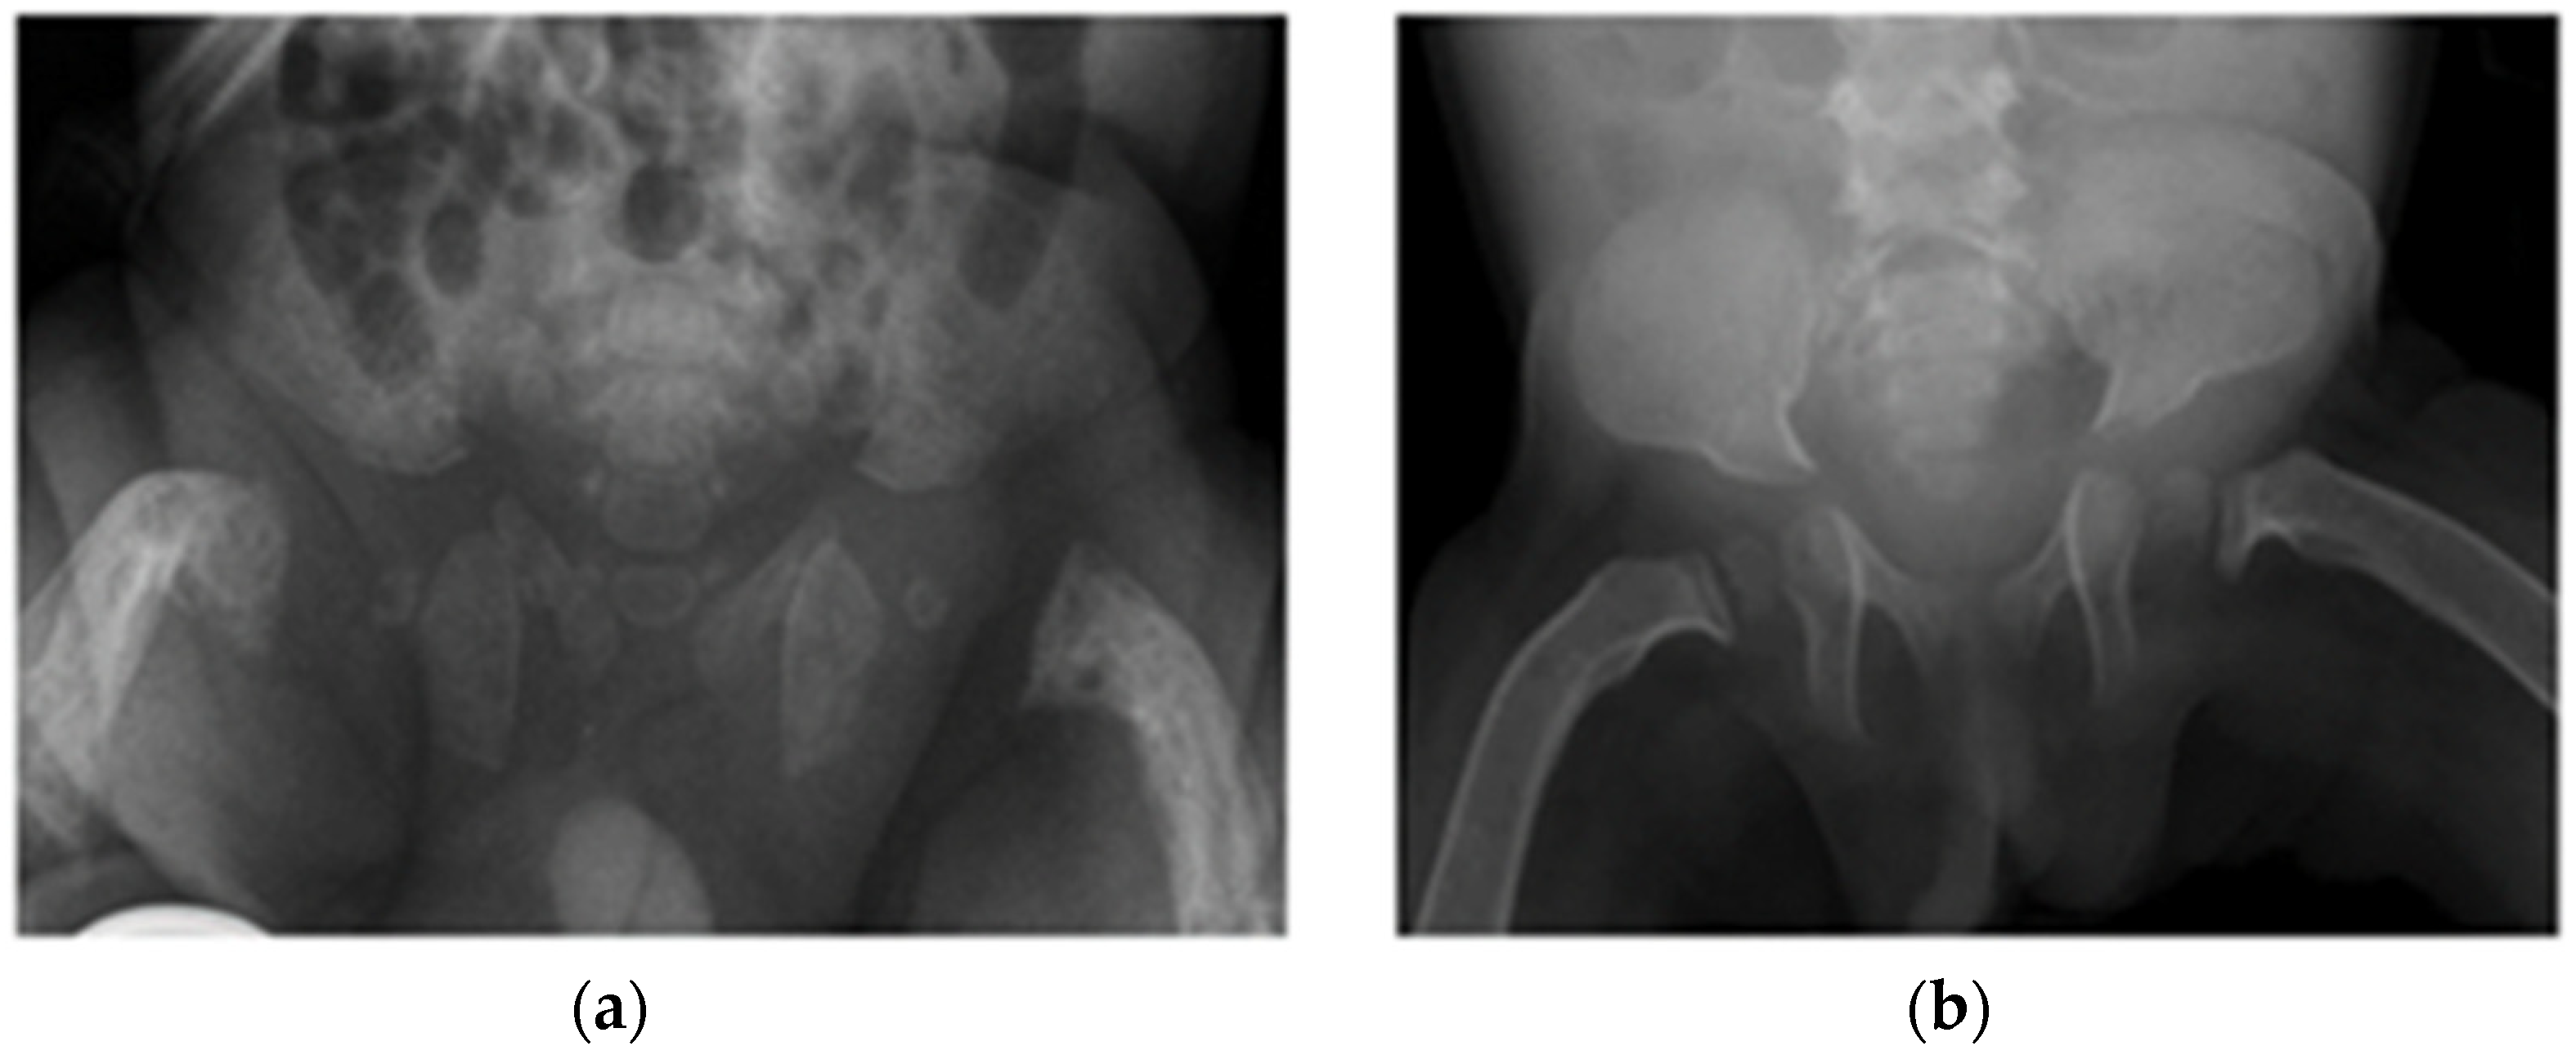

| Patient 1 | Antenatal fractures of long bones | 25 | 2.46 | 1.65 | 434 | Not available in medical notes | All patients had features of HPT (Figure 1 and Figure 2), including:

| Vitamin D 600 IU, minimal handling until 1 year of age |

| Patient 2 | Antenatal fractures of long bones | 119 ↑ | 2.36 | 1.17 | 1540 ↑ | 66.7 | None | |

| Patient 3 | No fractures | 72 ↑ | 2.45 | 1.96 | 1063 ↑ | 48 (reference range > 15 mmol/L) | None | |

| Patient 4 | Acute fracture of the proximal left humeral neck (Figure 3a), antenatal fractures | 252 ↑ | 2.32 | 1.62 | 1007 ↑ | 121 | Vitamin D 600 IU, minimal handling for 5 month | |

| Patient 5 | No fractures | 110 ↑ | 2.31 | 1.3 | 1256 ↑ | 30 ↓ | Vitamin D 1000 IU, re-evaluation planned in due course |